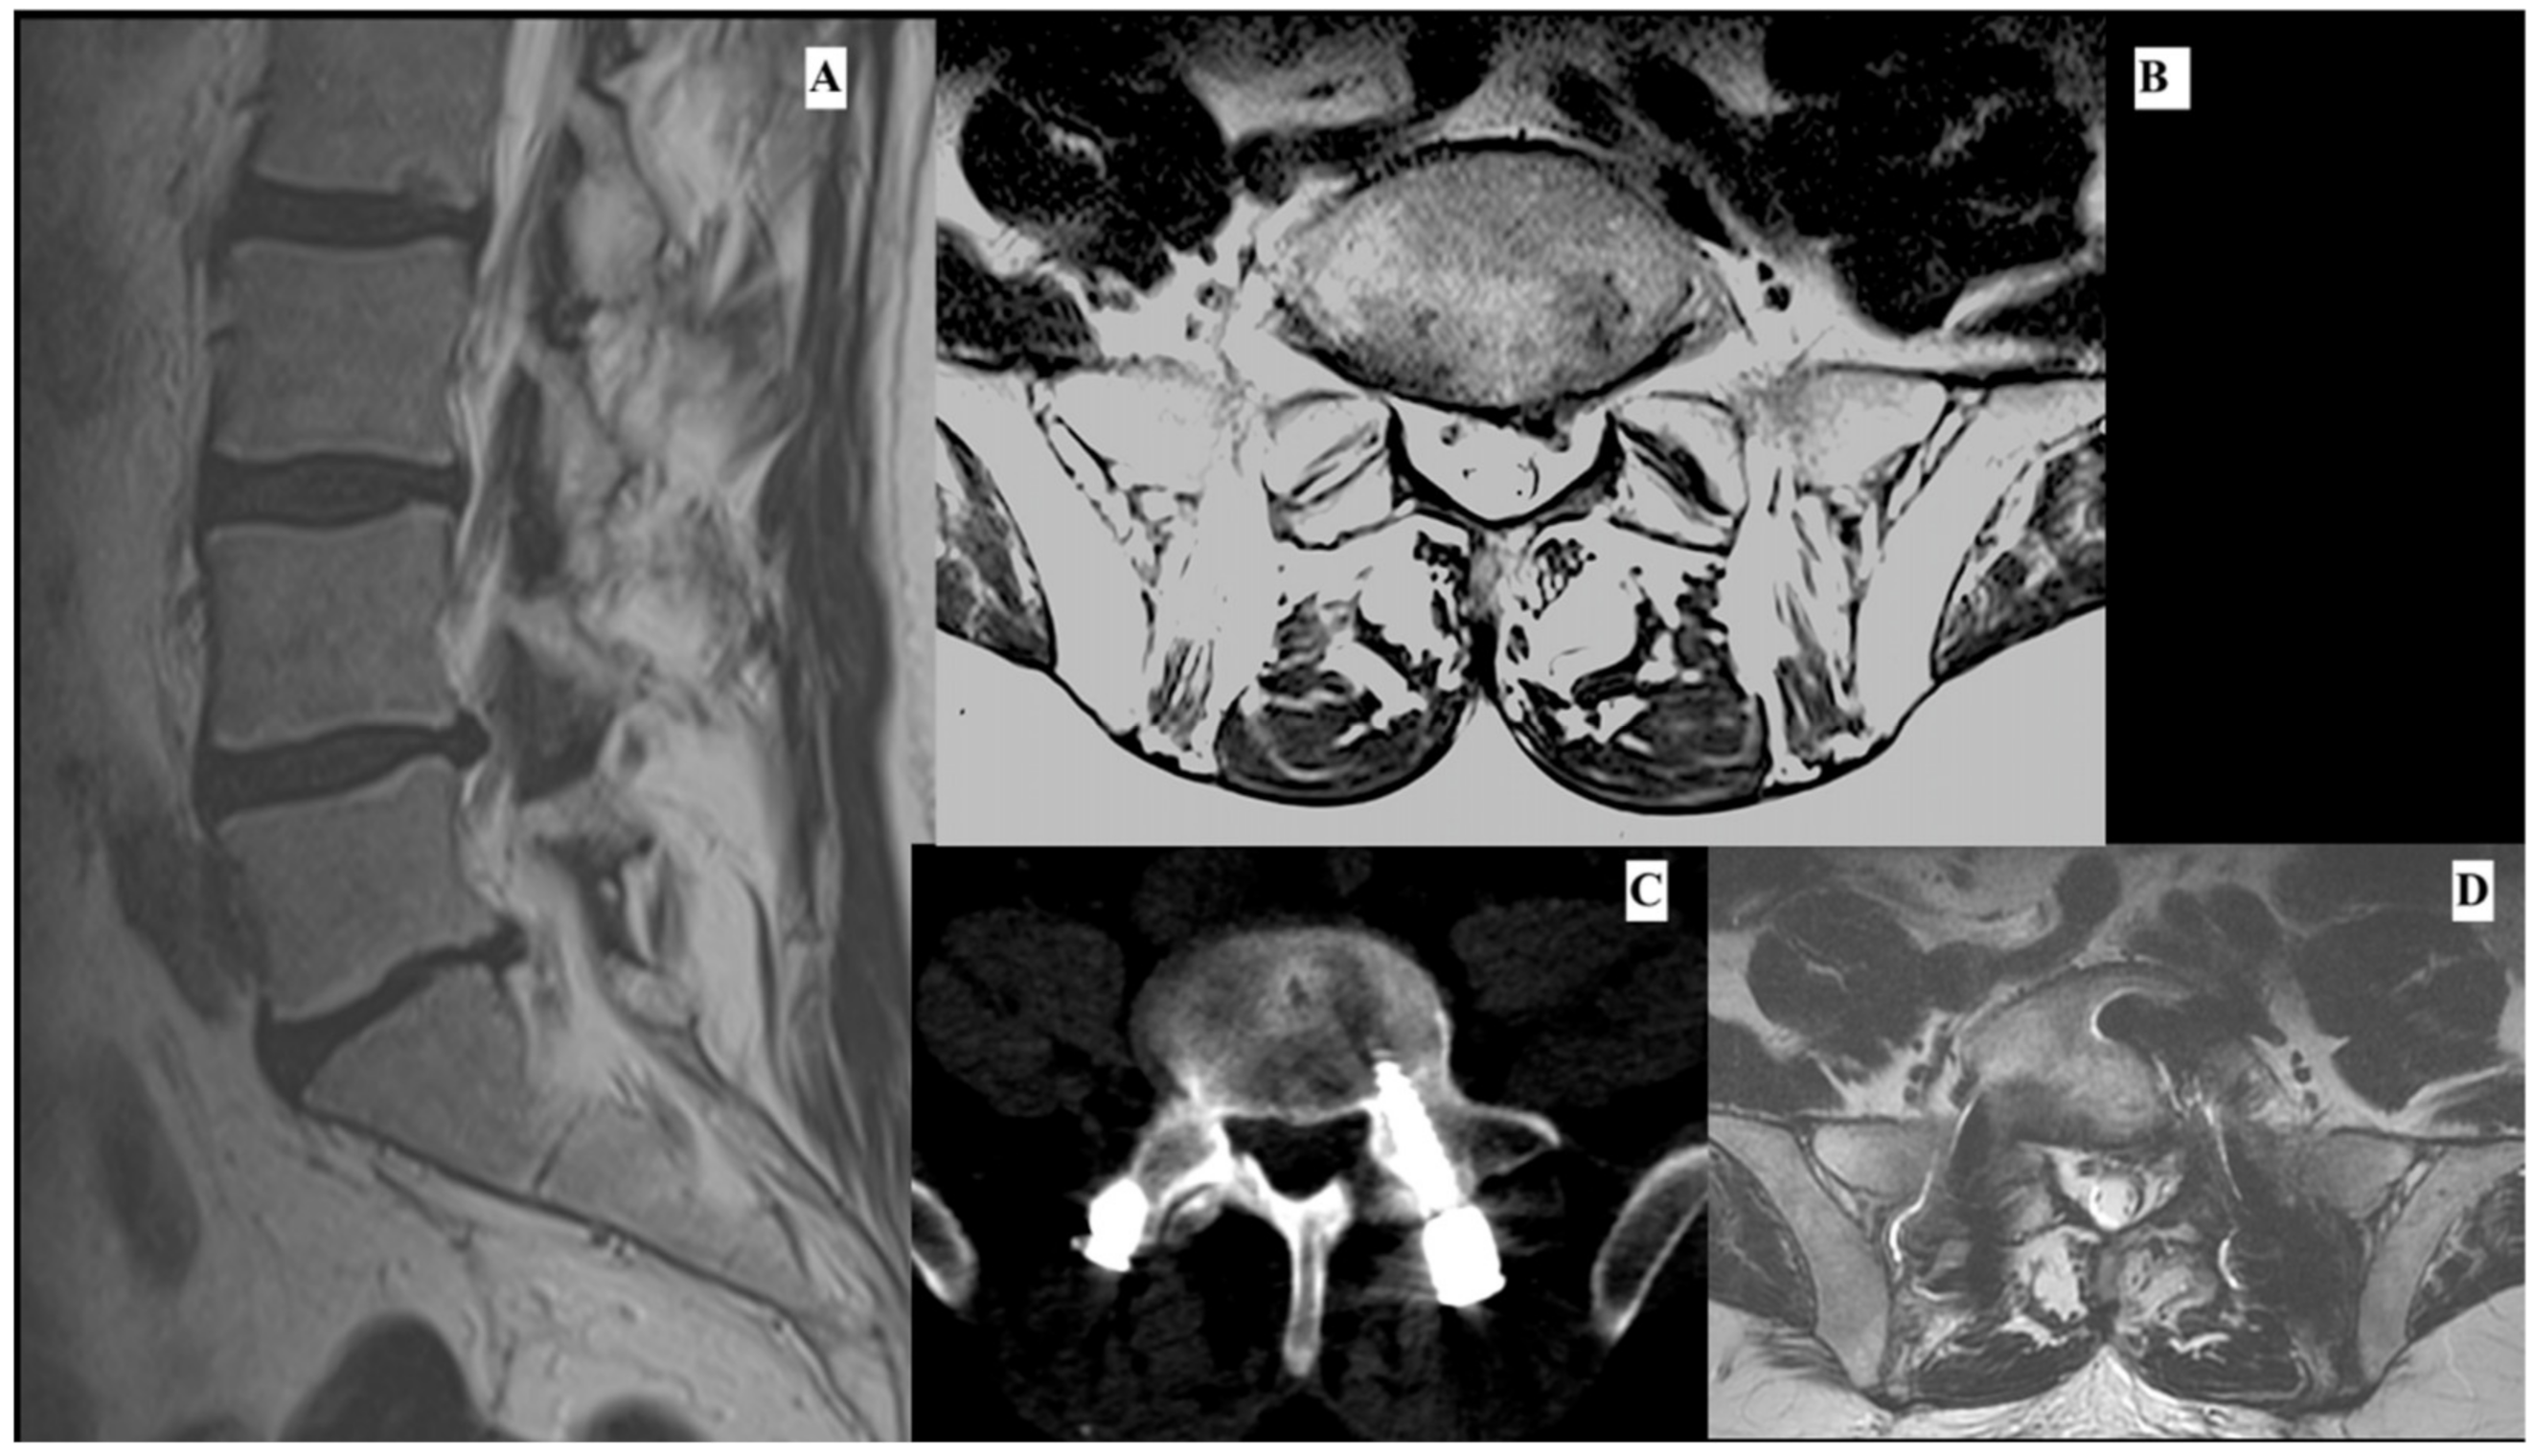

3.2. Representative Case

Postoperative Period

| Our case | 1 | L5-S1 | Discectomy + Lumbar spine stabilization | Not known | Improvement after 2 months |